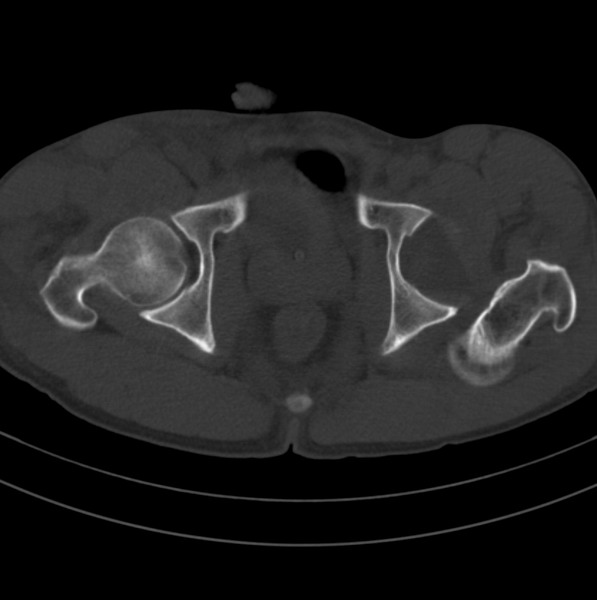

标题: CT18589:股骨头囊状阴影怎么下结论?

男、53

股骨头内的囊状阴影怎么下结论?

1.左髋后脱位。

2.囊状影考虑退变。

左侧髋关节后脱位;左侧股骨头疝窝。